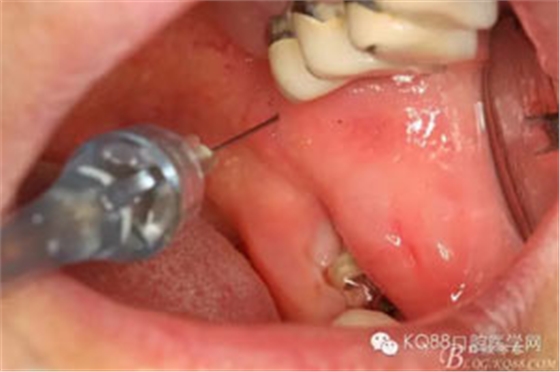

圖3. 采用局部無(wú)痛下牙槽神經(jīng)阻滯麻醉+38浸潤(rùn)麻醉

圖4. 外加38局部浸潤(rùn)麻醉、